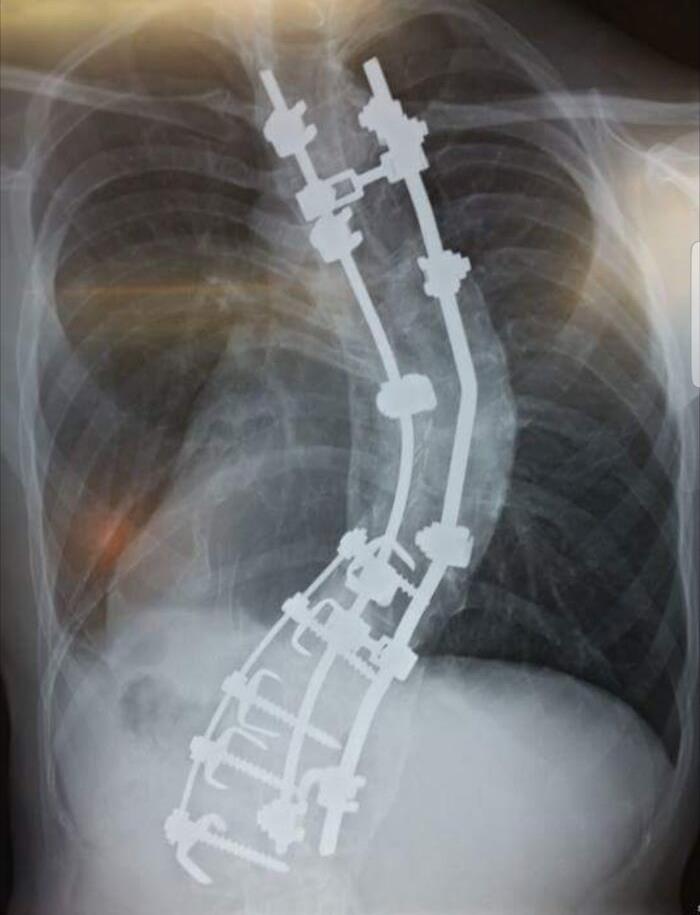

Mi columna vertebral. Entré para la cirugía midiendo 1,78 m, al salir medía 1,88 m, se supone que debería medir 2 m